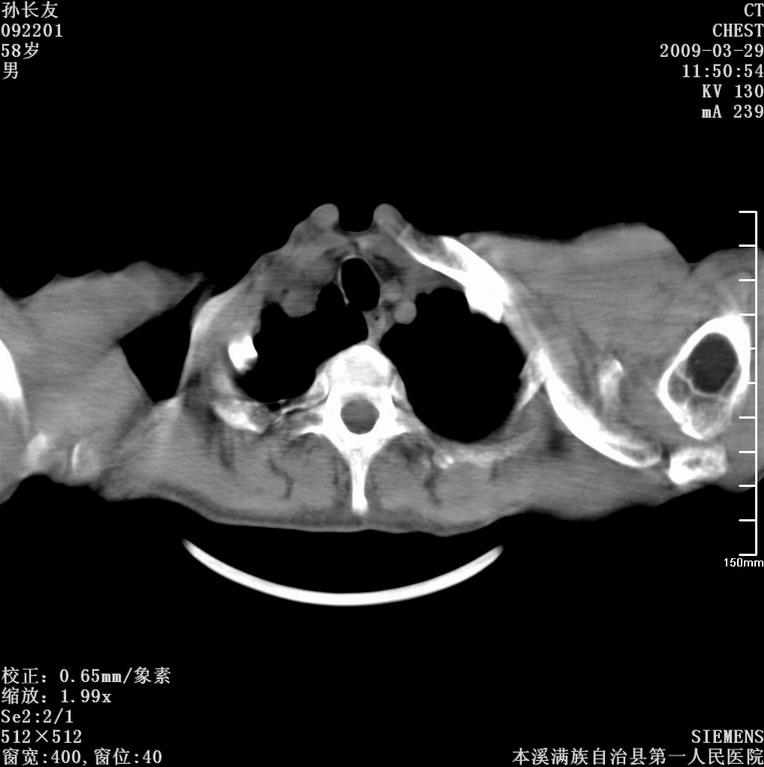

以下是引用liaoqiang在2009-3-30 8:29:00的发言:[br]所上传的层面示气管未见确切异常。

以下是引用bmw011在2009-3-30 12:09:00的发言:[br]所上传的层面示气管未见确切异常。